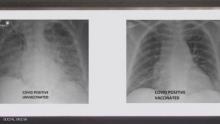

ملقح وغير ملقح.. صور الأشعة تكشف أثر كورونا على الرئتين

الصور الأولى (يمين) لرئتي شخص ملقح والثانية لشخص غير ملقح

البشام الإخباري/ نشر الطبيب العربي في الولايات المتحدة، غسان كمال، صورة تظهر الفرق بين رئتي شخص جرى تطعيمه ضد فيروس كورونا ورئتي شخص آخر لم يتلق التطعيم، مشيرا إلى أن الاثنين أصيبا بفيروس كورونا.